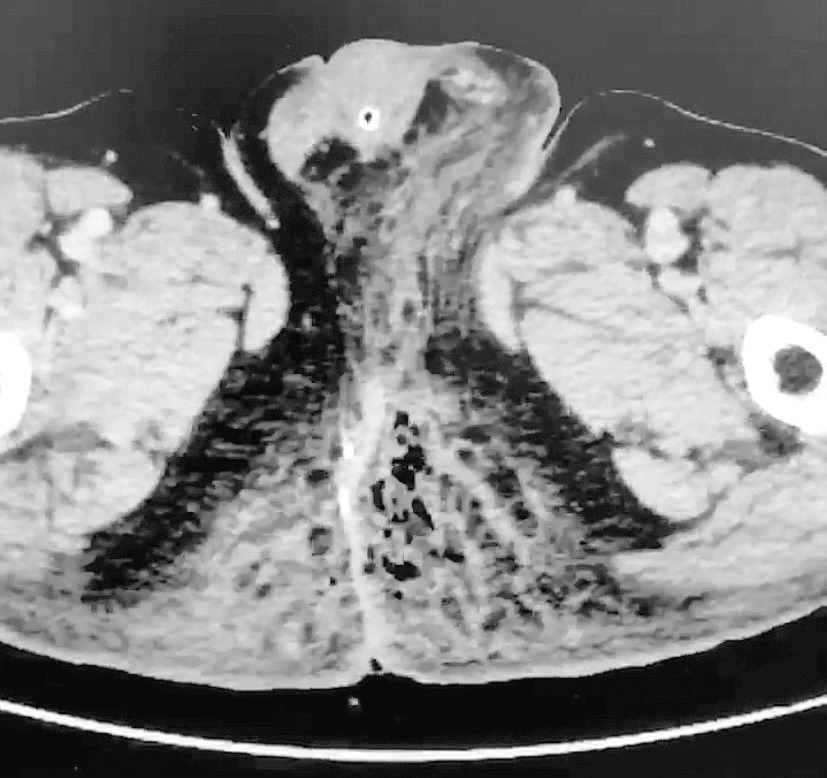

Il s’agit d’une urgence, car elle peut rapidement évoluer vers une défaillance multiviscérale. Il est important de ne pas méconnaître ce diagnostic ; en effet, les signes locaux du début ont une allure banale mais peuvent rapidement évoluer. Ainsi, le placard cutané, initialement érythémateux et œdémateux, devient ensuite infiltré et d’extension rapide vers le scrotum, les plis inguinaux, les lombes, etc. Le crépitement sous-cutané et le suintement verdâtre fétide caractéristiques sont tardifs. À ce stade, les signes systémiques (fièvre ou hypo­thermie, collapsus, confusion, etc.) sont quasiment constants. La mise en évidence de « bulles » en tomodensitométrie (fig. 2) est également caractéristique.